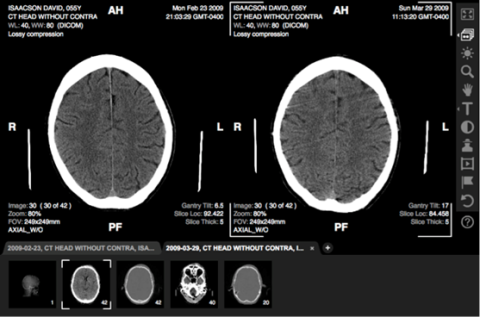

ACTUAL SCREENSHOTS OF TEST PATIENT IN Life Image: